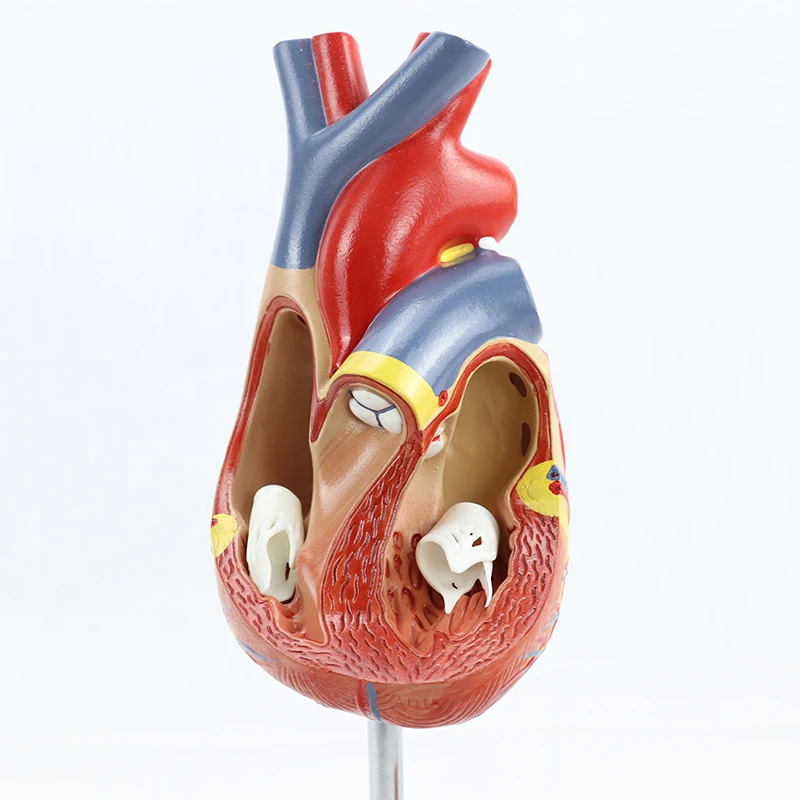

Фотографии и 3D-модели анатомии сердца человека